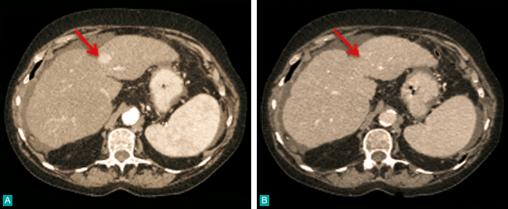

La Revue du Praticien - Jean-Frédéric Blanc Scanner. Avec hypervascularisation intense au temps artériel (A) et lavage (wash-out) au temps portal tardif (B).CHC sur foie de cirrhose.